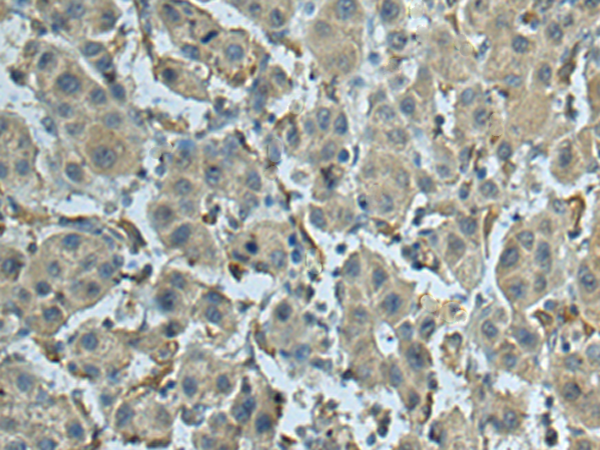

分类: 科研抗体货号: P10064别名:应用: IHC反应种属: Human, Mouse